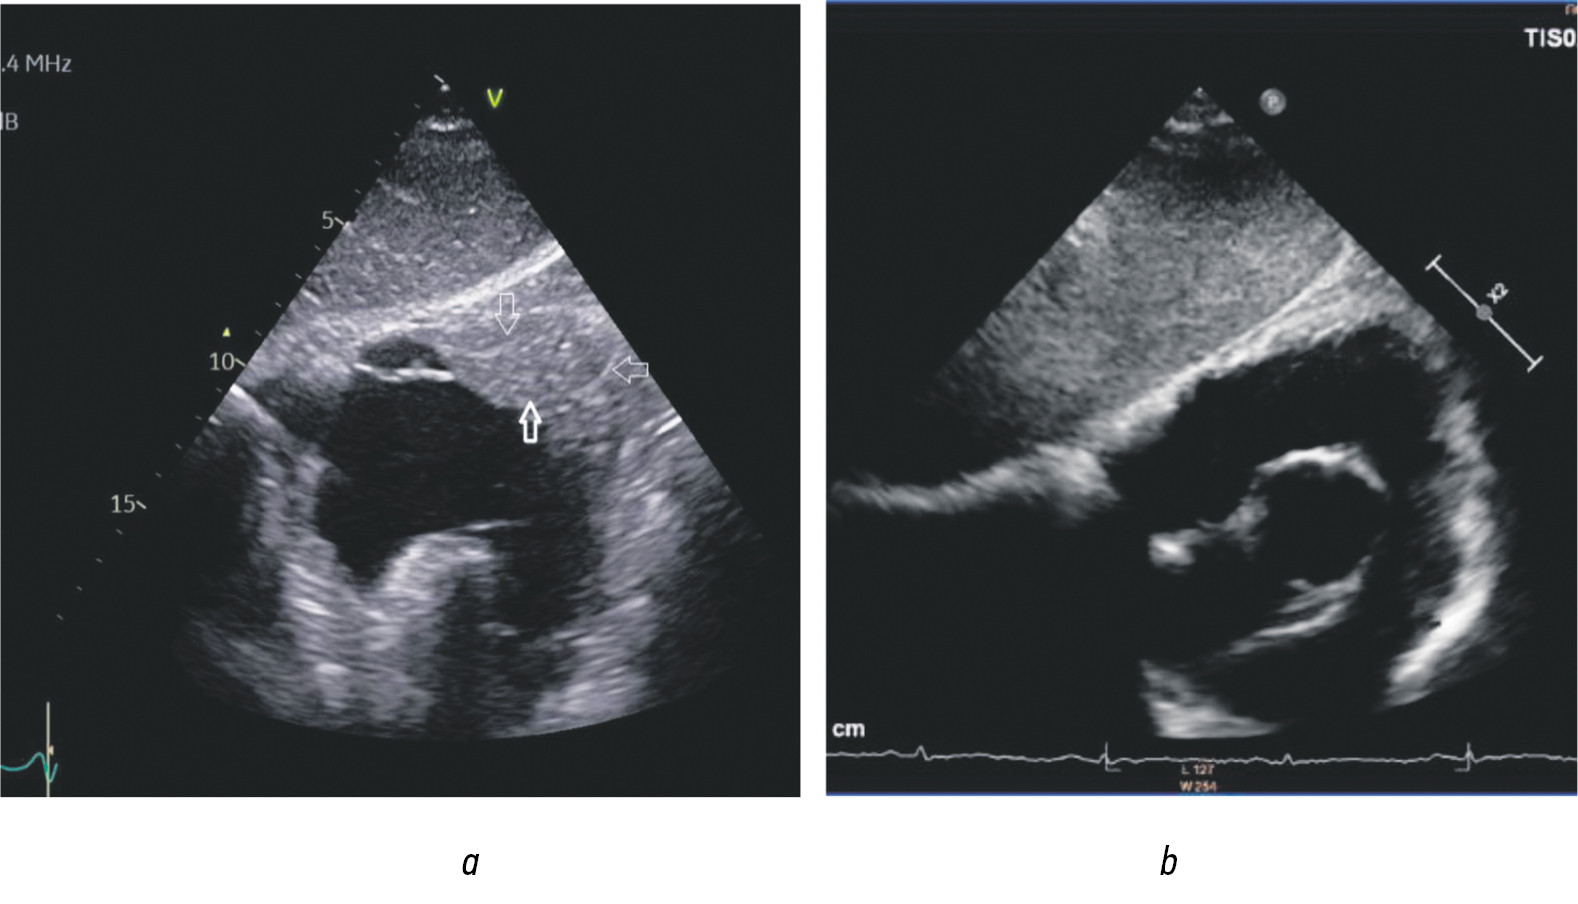

EchoCG showed hypercontractility of the basal and mid-LV segments associated with local akinesia of the apex (Merlon’s sign) and significant wall masses, which were initially believed to be extensive thrombotic deposits. These masses were localized in the area of the fixed apex and in the protrusion of myocardium with preserved contractility (Fig. 5). A similar condition was observed in the region of the outflow tract and the apex of the right ventricle (Fig. 6). LV systolic function was preserved. No echocardiographic evidence of severe diastolic dysfunction was noted.

Fig. 5. Echocardiogram of Loeffler endomyocarditis of the LV. Four-chamber view, apical approach. The arrows indicate wall masses in the area of the akinetic apex and in the projection of myocardium with preserved local contractility. The border between the myocardium and myocardial projections is clearly visible. The wall masses and myocardium have different densities, and there is an obvious boundary between them. Vertical arrows indicate extensive wall masses initially believed to be thrombus; horizontal arrow indicates LV myocardium

Fig. 6. Echocardiographic changes in the right ventricular outflow tract: a — short-axis view at the level of the aortic valve, subcostal approach, reveals parietal masses located in the outflow tract of the right ventricle, indicated by the lower arrow. The arrows above and to the right delineate the myocardium of the right ventricle and a clear boundary between the myocardium and the parietal deposits. For comparison; panel b — displays the same section from a healthy individual,demonstrating a non-thickened right ventricular myocardium absent of pathological parietal masses